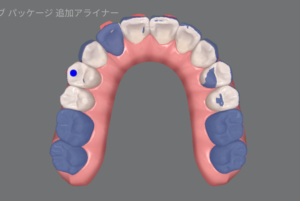

最終的には、こんな歯並びになる予定です。

何が変わったのか分かりづらいので、こちらもご覧ください!

青が追加治療前の状態、白が追加治療後の状態を表しています。

右上2番目の歯を前に出す動きや、下の歯を全体的に寄せる動き、分かりづらいですが上の前歯の傾きを直す動きもしっかり組み込まれています。